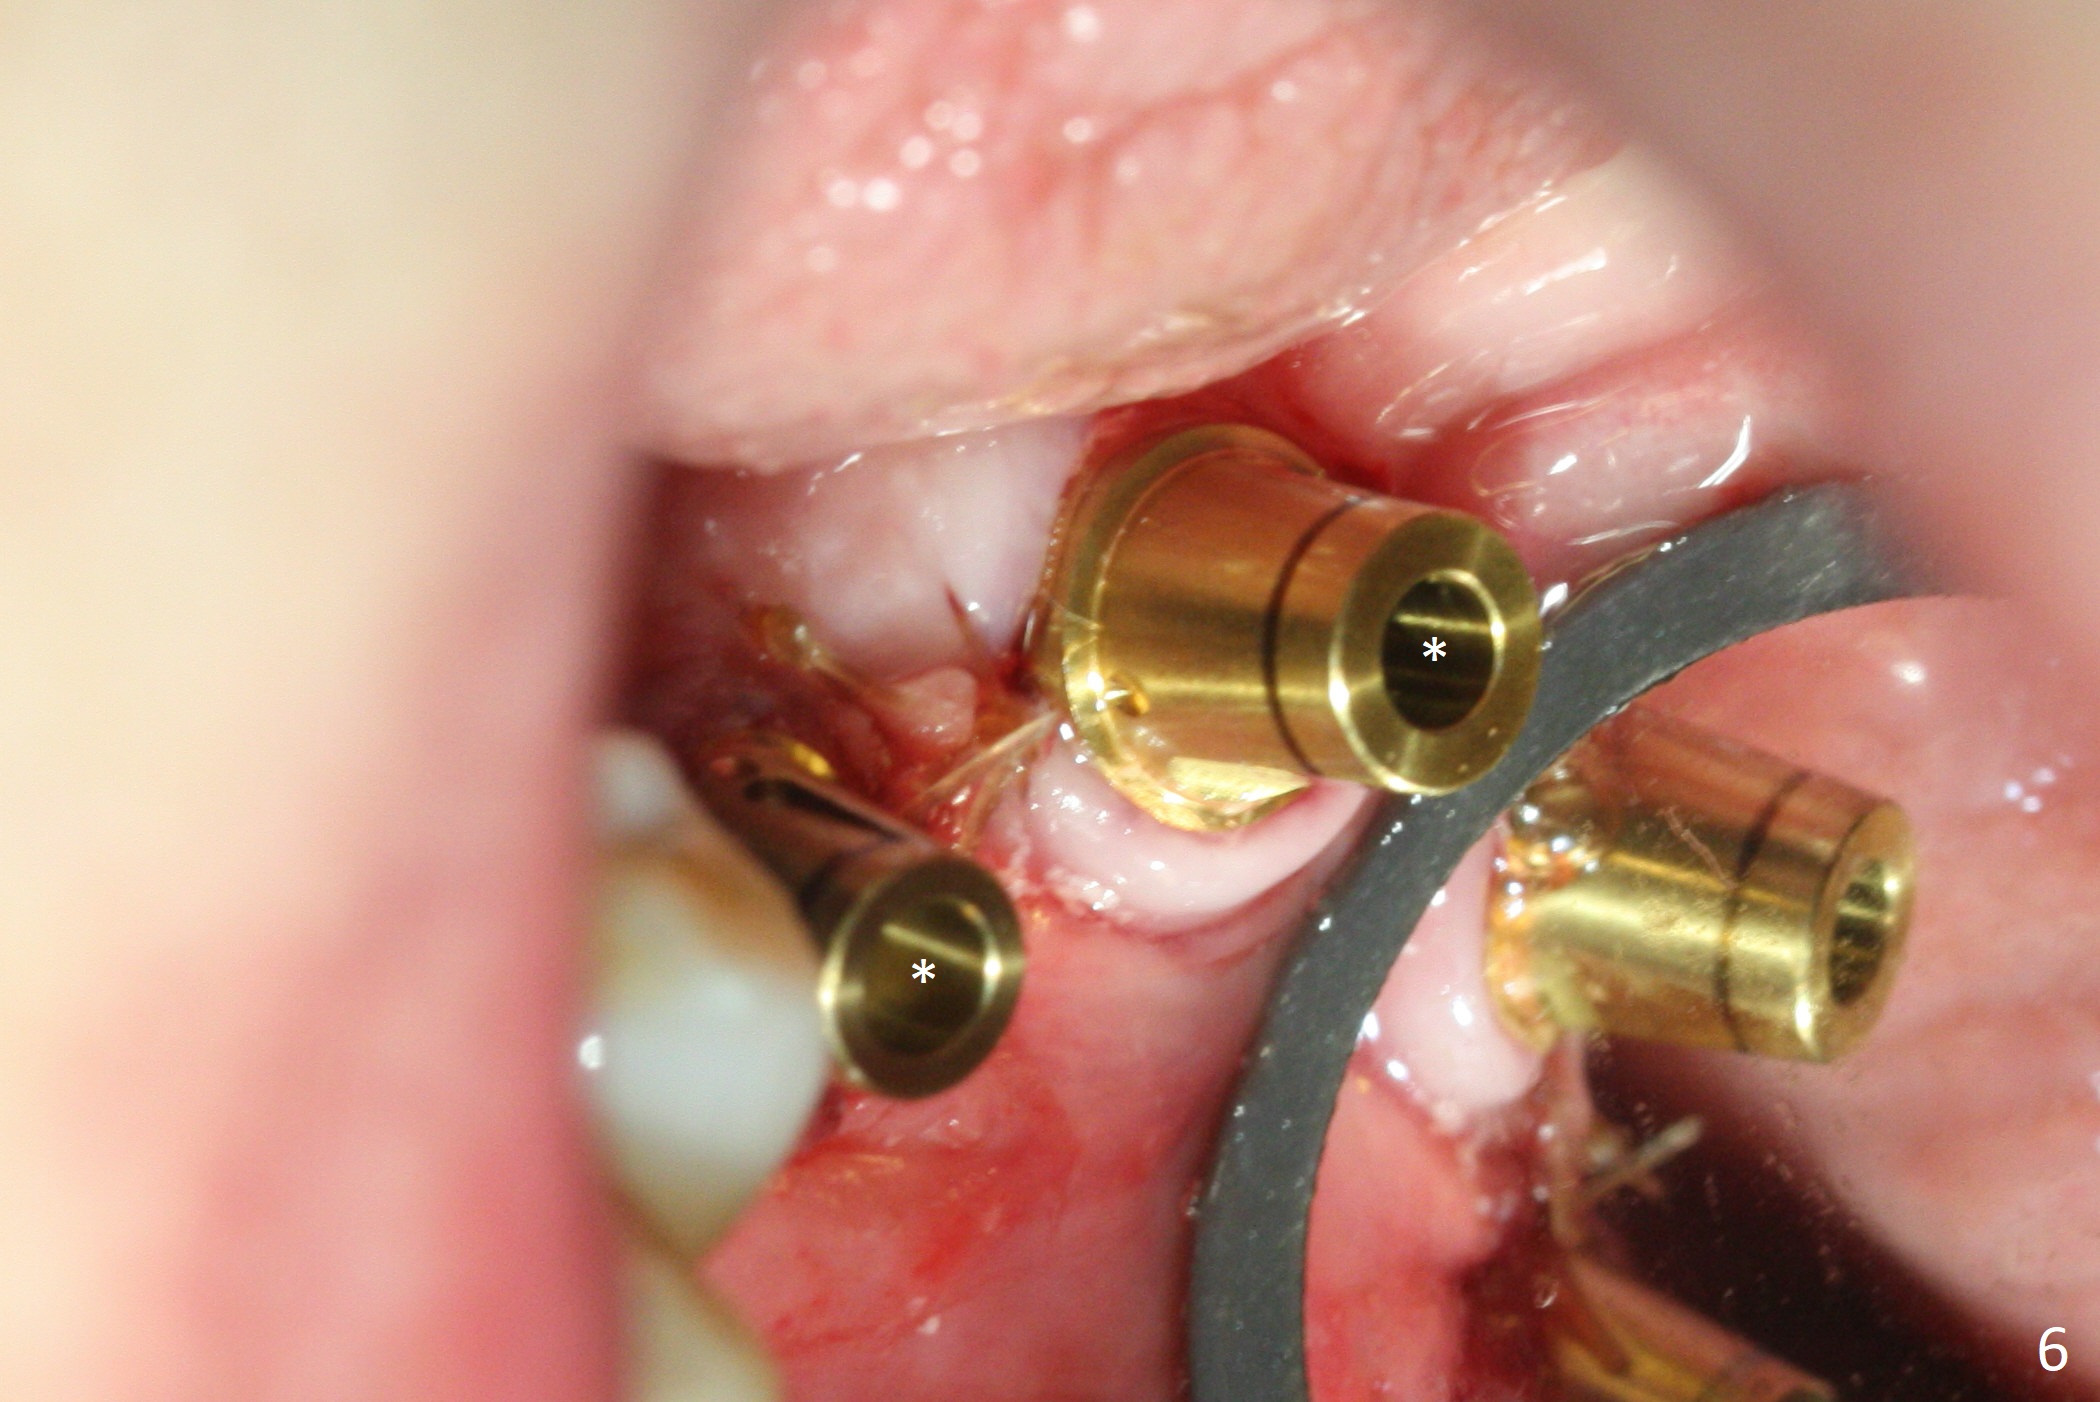

Preop photo shows severe mesial tilt of the tooth #18 (Fig.1). After extraction, the osteotomy is established in the apical end of the socket, where the buccolingual width is limited. It appears that an extra wide implant (5.9 mm) may perforate one of buccolingual plates. On the other hand, the buccal plate (Fig.2 double arrows) is intact and approximately 2 mm tall, whereas the lingual one is thin and lower. Initial osteotomy confirms that bone heights at #18 and 19 are 6 and 8 mm, respectively. Counting 2 mm of the buccal plate and bone graft lingually, a 8 mm long implant may be a practical option at the site of #18. After initial placement of two of 5x8 mm SM implants (Fig.3), the depth of the implant at #19 is adjusted twice (Fig.4,5). With placement of autogenous and allograft (Vanilla, Fig.5 *)) and abutments, a piece of cotton pellet is placed in each abutment well (access, Fig.6 *). Periodontal dressing is applied to the abutment wells for additional retention (Fig.7 *). Due to local poor oral hygiene, splinted provisional is fabricated 4 months postop (Fig.8) in preparation for limited orthodontic uprighting the tooth #20. The patient has pain with mastication at #18 eleven months post cementation (Fig.9). It appears that both of the implants should be removed with immediate replacement and bone graft. Prepare 4 PRF and sticky bone. The new implant will be 5.0 or 5.5x5 mm (Fig.10 green) with 2.3 mm platform (white). A block graft will be harvested from the ipsilateral ramus using 9/8 and 6/5 mm trephine burs for 2-3 mm in depth (Fig.11 blue). The ring graft will be seated around the platform over the implant (Fig.12).